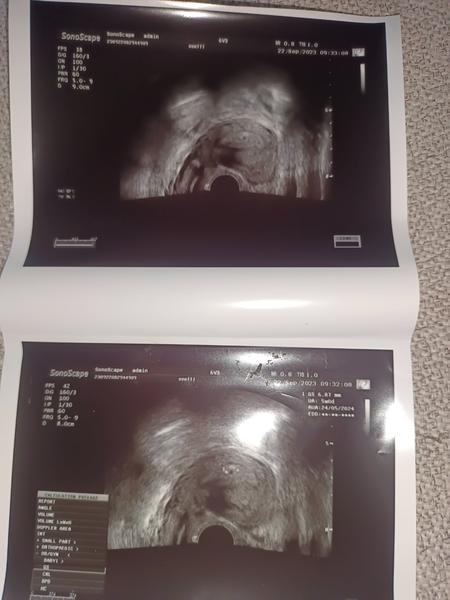

Tak holky před nedávnem jsem měla diskuzi o tom, jestli na testu vidíte ducha, čárka na testu sílila, poté z ckear blue to bylo vic než jasné, byla jsem u doktora s tím že mi vyšel pozitivní test pan doktor odebral krev udělal ultrazvuk, na uktrazvuku pouze vyšší sliznice za dva dny později, viděl na uktrazvuku dutinku, kterou jsem teda také moc nemohla najít na fotce, můj doktor je vždy se vším rychle hotový, při mém minulém biochemickém těhotenství, kdy vlastně skončilo těhotenství dřív než začalo, dozvěděla jsem se že jsem těhotná pouze z krve a to bylo 40 HCg pozitivní což je ještě skoro nula nula prd... když jsem začala krvácet a poté šla na kontrolu oznámil mi špatnou zprávu velice necitlivě teda aspoň pro mě ani mě neprohlidnul...

Změnila jsem pana doktora vše mi na uktrazvuku vysvětlit, dokonce jsem u sebe měla jen drobný a kartu, a říkal že nevadí že přinesu příště, dál mi dvě fotky zatím teda jenom gestační váček, dle MS bych měla být 6 týden dle ultrazvuku 5+0 nález odpovídá týdnu, takže se teď hodně šetřím, snažím se jíst zdravěji a moc se nenervovat a nepřepínat, za 3 týdnů jdu znovu, snad už na mě bude mávat malý obyvatel❤️❤️